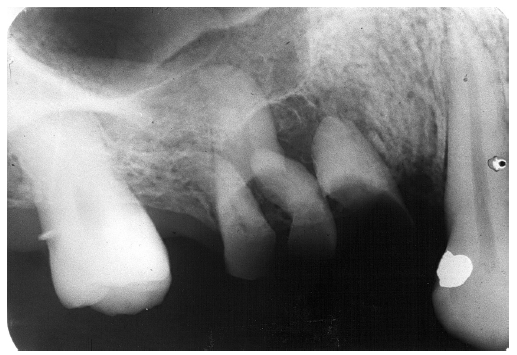

In Figure 4, recurrent caries appears at the mesial of tooth #3 and #4, and the distal of tooth #28. Also, note areas of interproximal caries on teeth #5-6.

Figure 4 - Recurrent Caries

Figure 4